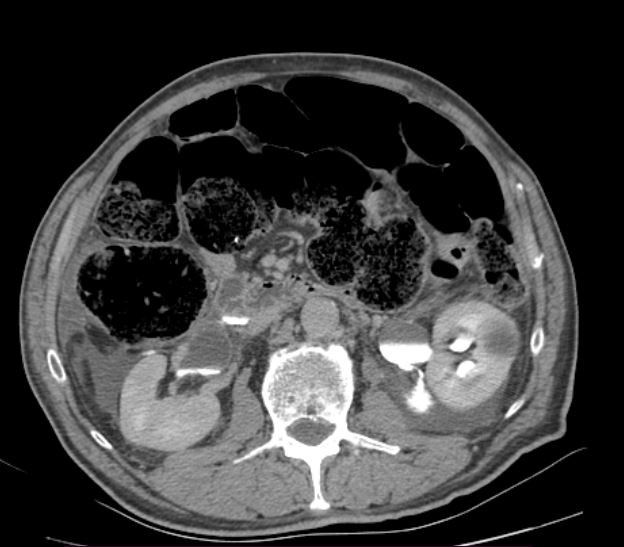

Following the intravenous contrast injection, in the post contrast series, the kidneys exhibited appropriate absorption and excretion of contrast media within the expected time frame (in a timely manner). However, it was observed that the patient had extrarenal pelvis bilaterally, cortical cysts bilaterally that didn’t interfere with the urodynamic, dilated ureters along with a dilated urinary bladder. Furthermore, in the adjacent kidney tissue, there was observed leakage of the contrast media from the renal pelvic lesions in both kidneys. There were no indications of trauma to the parenchymal organs within the abdominal region.

Figure 1. Free fluid in the surrounding kidney tissue.

Figure 2 and 3. As seen on the scans to the left, the surrounding free fluid dif. dx can mean urine, blood. On the scans to the right, the contrast media leakage is evident in the surrounding tissue, meaning there are lesions in the renal pelvis bilaterally.